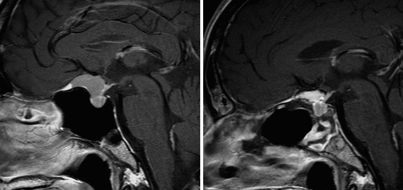

経鼻内視鏡手術の術前と術後

頭蓋底腫瘍に関しては、頭蓋咽頭腫や鞍結節髄膜腫などが対象となります。腫瘍が頭蓋内の深いところにあるため、これまでは頭を大きく開け、脳や神経、血管を押し分けて摘出する開頭手術が必要でした。しかし、腫瘍の大きさによっては鼻から手術を行うことで体の負担を少なく摘出が可能です。さらに経鼻手術では腫瘍の下からアプローチするので、脳や神経、血管などを押し分ける必要がないため、より負担が少なくなります。手術の際には、安全性を高めるためにナビゲーションや神経モニタリング、血管ドップラーを使用します。術後は翌日から歩行が可能で、問題なければ術後7日間で退院可能です。この手術における髄液漏の危険性は下垂体腫瘍の手術より高く30%と言われていますが、当院では、大腿部から採取した筋膜をパッチワークのように縫合することで髄液漏を完全に抑えることに成功しています。